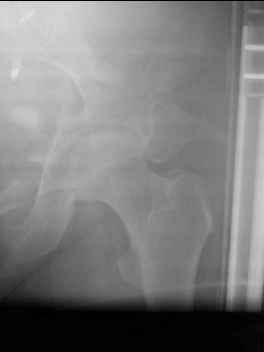

41 yo female , fall from 10 meters five days ago. Hemodynamically unstable on admission treated by angio and embolization and skeletal traction, with no external support. No associated injuries.

Based on CT scan the pt has a both column fracture with conminuted dome and displaced anterior column and a sacral Denis 1 fracture with a displaced left ala. I think the best approach for the acetabular fracture is ilioinguinal with Smith-Petersen extension but don't know exactly the sequence . Will you start with the sacral fracture? Which technique?